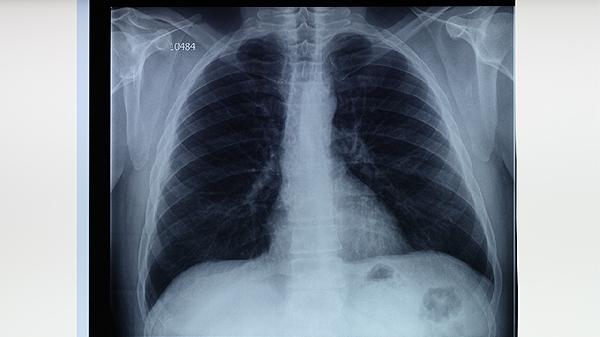

肺结核患者护肝药物需严格遵医嘱使用,常用护肝药物主要有水飞蓟宾胶囊、复方甘草酸苷片、双环醇片、谷胱甘肽片、多烯磷脂酰胆碱胶囊等。肺结核治疗中抗结核药物可能引起肝损伤,护肝药物需根据肝功能检查结果个体化选择。